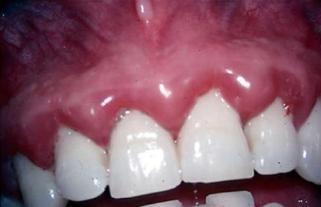

- Free gingiva: Inflammatory、hypertrophy、出血

- CP: 刷牙 Bleeding

- Bleeding?